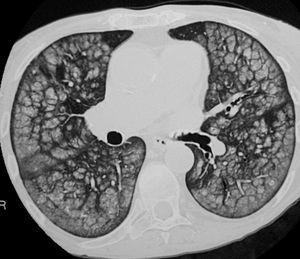

La paciente ingresó en varias ocasiones por descompensación respiratoria secundaria a infección bronquial. Clínicamente presentaba disnea a esfuerzos moderados. En la actualidad presentaba nefropatía crónica del trasplante, por lo que se planteó un nuevo trasplante y se consultó a neumología para valorar la enfermedad pulmonar y el riesgo quirúrgico secundario. La radiografía de tórax mostraba un patrón nodulillar difuso bilateral, sin pérdida de volumen pulmonar (fig. 1). La exploración funcional respiratoria puso de manifiesto una limitación moderada al flujo aéreo e intensa reducción de la transferencia al CO. La capacidad vital forzada (FVC) era de 2,20 l (un 74% del valor de referencia [VR]), el volumen espiratorio forzado en el primer segundo (FEV1) de 1,37 l (63% del VR), el cociente FEV1/FVC del 62%, la capacidad residual funcional del 88% del VR, el volumen residual del 110% del VR, la capacidad pulmonar total del 91% del VR, la capacidad de difusión de CO (DLCO) del 41% del VR y DLCO/volumen alveolar del 46% del VR. Los valores de la gasometría arterial en reposo fueron: presión arterial de oxígeno (PaO2) de 82 mmHg, presión arterial de anhídrido carbónico (PaCO2) de 45 mmHg, pH de 7,41 y bicarbonato de 27 mEq/l. La TAC torácica demostró múltiples calcificaciones distribuidas en partes blandas de forma difusa, principalmente localizadas en el tejido subcutáneo; adenopatías calcificadas en la región traqueobronquial izquierda; calcificaciones aórticas y de anillo valvular mitral, y múltiples calcificaciones vasculares arteriales. En el parénquima pulmonar se evidenciaron múltiples infiltrados en vidrio deslustrado y de distribución centrolobulillar, que afectaban difusamente y de forma extensa ambos campos pulmonares (fig. 2). Todos estos hallazgos eran muy indicativos de calcificaciones metastásicas en relación con el hiperparatiroidismo terciario, secundario a la insuficiencia renal crónica.

Fig. 2. Tomografía axial computarizada de tórax que muestra la presencia de múltiples infiltrados en vidrio deslustrado y distribución centrolobulillar, indicativos de calcificaciones metastásicas.